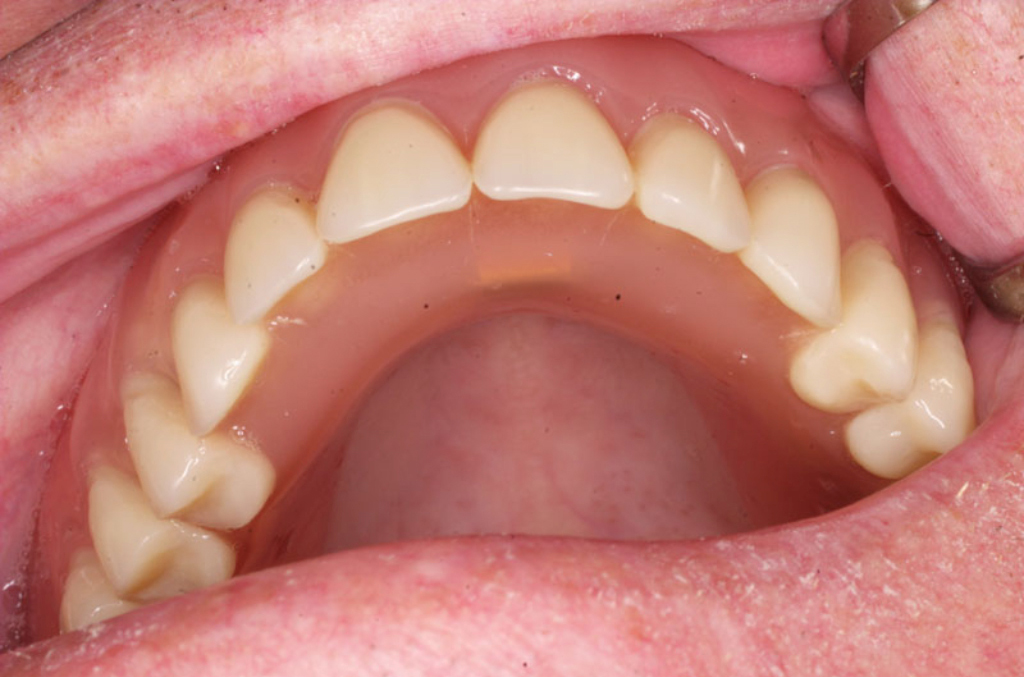

Klasickým příkladem a indikací pro použití implantátu je ztráta jednoho zubu (v tomto případě v předním – frontálním úseku) v jinak zdravém, nepoškozeném chrupu.

Nejčastější příčinou takové ztráty je sportovní nebo dopravní úraz.

Náhrada jednoho zubu pomocí implantátu je možná také v postranním úseku chrupu. Při ztrátě většího počtu zubů ve frontálním nebo postranním úseku může být mezer uzavřena větším počtem jednotlivých implantátů.

Při ošetření pomocí jednotlivých implantátů zůstávají sousední zuby neporušené – intaktní. Při klasickém ošetření pomocí můstků musejí být tyto zuby obroušeny!